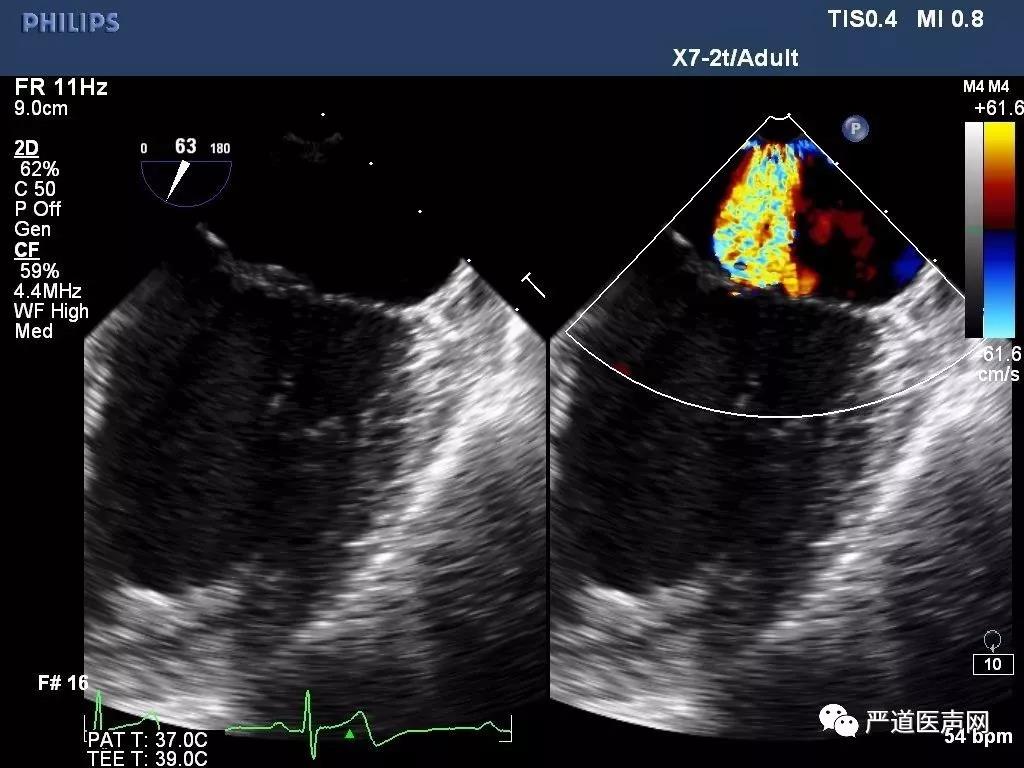

高龄老年男性患者,超声提示二尖瓣后瓣及前瓣脱垂伴重度反流,有明确临床症状,反复出现心衰临床表现,并具有多种合并症。经过讨论,该患者行传统外科手术风险较高,选择性微创ValveClamp治疗。围手术期经食道超声(TEE)确认二尖瓣退行性病变,前瓣后瓣A2/P2脱垂伴重度反流,脱垂区域宽度12mm,手术采用全麻左前胸3cm微创切口,通过心尖如路16F血管鞘完成,无需体外循环及心脏停跳,在TEE引导下准确将上海捍宇医疗创新研发的ValveClamp准确释放于A2/P2脱垂区域,行介入缘对缘(edge-to-edge)修复,整个手术过程顺利,植入时间仅25分钟,无明显失血,术后TEE提示二尖瓣反流即刻为极微量,二尖瓣双孔化形成,二尖瓣平均跨瓣压差仅为2mmHg,瓣口无狭窄,临床效果满意。

图1: TEE提示二尖瓣重度反流